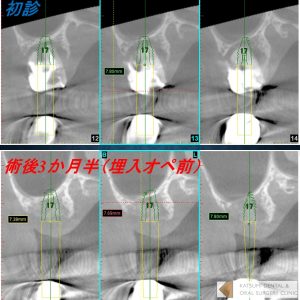

提示の症例では、更に「ソケットリフト」という骨を槌打して骨を挙上させかつ圧縮して骨密度を高める術式を併用することによって、よりインプラントがしっかり安定できるようにしております。